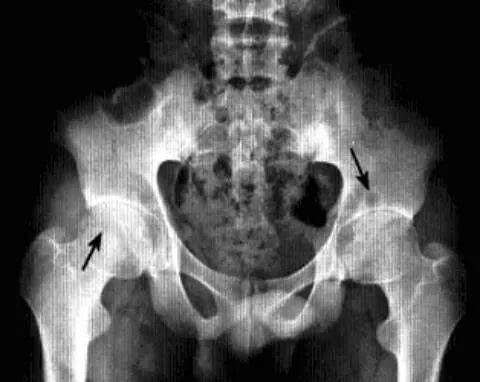

影像诊断:X线平片是基本检查方法,直立骨盆正位及髋关节侧位片。

平片:①凸轮撞击型,正位片示头颈连接处扁平,呈“左轮枪柄”样畸形,侧位片示股骨头颈凹陷减少,*边缘角变小<16度,②钳夹撞击型,髋臼窝过深,髋臼后倾,呈相交8字征,偏心距缩短<9mm。

CT:三维CT可测量股骨头颈连接处前外侧偏移量减低,股骨头颈联合处前上缘可见骨性突起。

MRI:股骨头颈凹陷减少(α>50°),股骨颈宽度与股骨头半径比率增大,髋臼后倾。盂缘退行性改变,撕裂、囊肿,关节间隙后期出现狭窄,周围肌肉炎症。